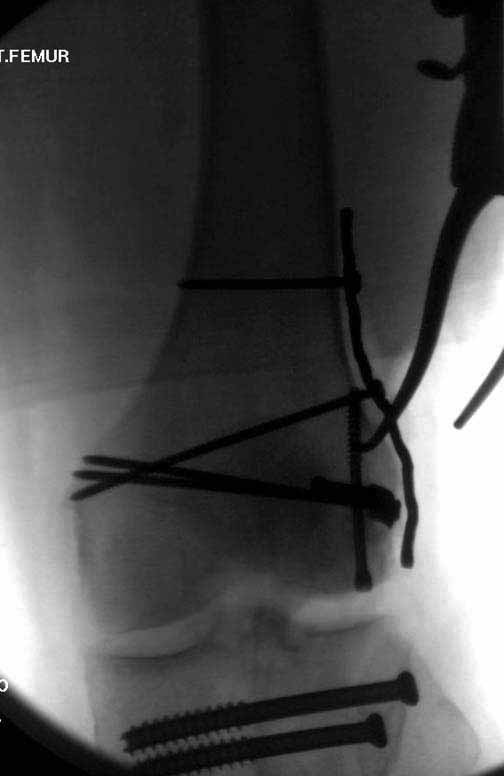

Ответ на эту часть Вашего поста – вложенный файл. Больная оперирована неделю назад по поводу открытого перелома дистального эпиметафиза бедренной кости. После операции она идёт в рентгенкабинет для выполнения послеоперационной контрольной рентгенографии, представленной на слайдах 10 и 11. Узнав, почему её фотографируют, просила передать Вам, Антон, привет.

наружный мыщелок не дорепонироавн - это приводит к вальгусной деформации оси коленного сустава, очень критично для последующей функции.